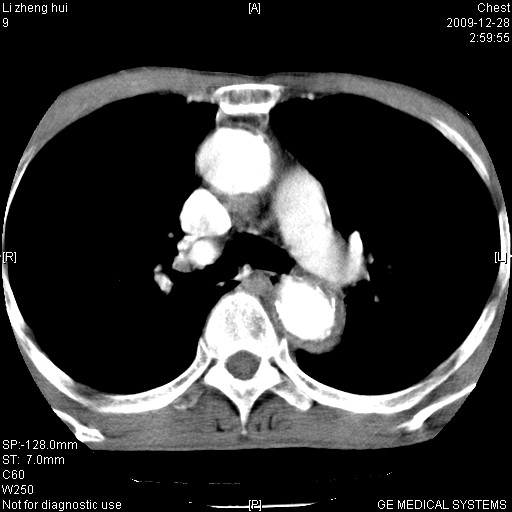

标题: CT23859:胸主动脉瘤

男  79岁 胸部痛急诊入院,晚上做的增强

考虑主动脉瘤?(增粗、钙化、壁血栓?)

动脉瘤伴附壁血栓

1)考虑胸主动脉壁间血肿或夹层动脉瘤。2)多发性肝囊肿。

1)考虑胸主动脉附壁血栓或夹层动脉瘤。2)多发性肝囊肿。